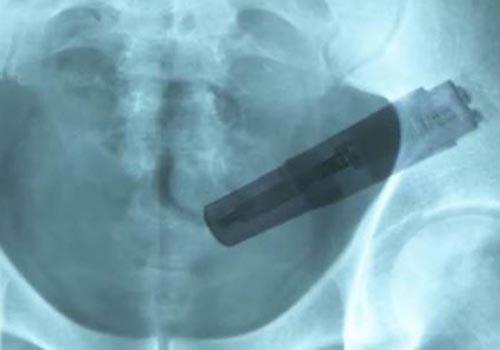

Raio- X do homem | Foto: Reprodução

Entretanto, depois de um raio- X, tornou-se evidente o motivo para ele ter sentido algo estranho na área abdominal enquanto estava em casa. "Pudemos ver, perfeitamente, um grande objeto instalado no intestino grosso", disse a enfermeira Stevey Pope, que tratou o homem. ?Esta é a primeira vez que eu encontrei um vibrador, ainda funcionando, no interior de alguém".